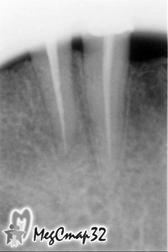

После проведенных операций во второе и третье посещения были сделаны

контрольные снимки (сн.№2 сн.№3) на которых стало заметно

уменьшение воспалительных явлений.